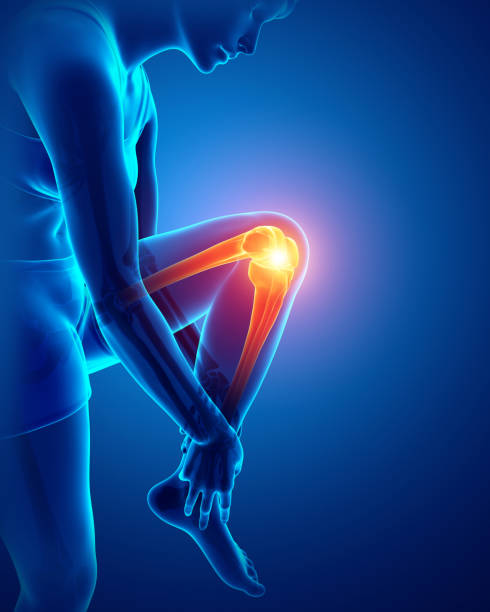

If you’re dealing with knee pain from sports, training, or everyday movement, the hardest part usually isn’t the pain itself.

Knee pain isn’t one thing — it can come from different causes depending on movement and activity.

🧠 Common Conditions Behind Knee Pain

These are some of the most common diagnoses athletes deal with:

Knee pain is one of the most common issues athletes deal with — but also one of the most misunderstood.